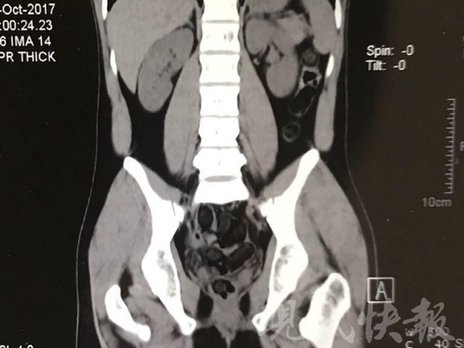

運毒小伙:希望被判處死刑

由于毒品在體內一旦泄露有可能致命,警方第一時間將阿永帶到醫(yī)院進行檢查。CT 掃描的結果顯示,阿永體內布滿了密密麻麻的白色圓柱狀固體,就像一粒粒的蠶蛹。在南京市公安局鼓樓分局二板橋派出所,阿永分四次排出了毒品,毛重369.99克。經訊問,阿永交代了自己全部的犯罪事實。目前,阿永已被刑事拘留。